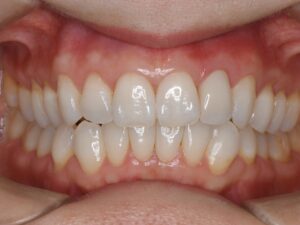

ジルコニアオールセラミッククラウンによる再補綴を行った。当然ながら、歯肉圧排(2重圧排)とシリコン印象による精密印象を行っている。

歯の色合い、歯茎の反応も良く、自然な感じで仕上がっている。